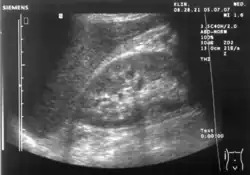

Ultralydsscanning

Ultralydsscanning (kan også staves med enkelt s, ultralydscanning) anvendes bl.a. til at tage billeder af fostre samt indre organer. En ultralydsscanner fungerer på samme måde som et ekkolod, som fiskere anvender til at lokalisere fiskestimer. Ultralyd udsendes i impulser fra en transducer og kastes tilbage mod en måler i apparatet, når de møder væv. Man kan derved danne sig et billede af eksempelvis et foster eller et indre organ.

Gravide kvinder tilbydes forskellige former for fosterdiagnostik, hvor ultralydsscanninger indtager en central plads. Omkring uge 13 i graviditeten tilbydes en nakkefoldsscanning, hvor tykkelsen af fosterets nakkefold måles på et ultralydsbillede. Den målte tykkelse bruges i udregningen af risikoen for at fosteret har Downs syndrom. Risikotallet bruges som beslutningsgrundlag for, om der skal foretages en invasiv undersøgelse i form af en fostervandsprøve eller en moderkageprøve. De invasive undersøgelser giver sikkert svar på, om der er kromosomfejl hos fosteret, men de indebærer en risiko for at fremprovokere en abort.

Ca. halvvejs i graviditeten (omkring uge 20) tilbydes en såkaldt misdannelsescanning. På dette tidspunkt er alle fosterets organer dannet, og dermed kan ultralydsbillederne afsløre, om der er misdannelser i lemmer eller organer. Dette giver mulighed for at foretage en abort, hvis fosteret er misdannet på en måde, så det ikke kan overleve uden for livmoderen, eller at tage passende forholdsregler hvis barnet har misdannelser, f.eks. hjertefejl, der kræver behandling umiddelbart efter fødslen. Ved misdannelsesscanningen er det også muligt med en vis sikkerhed at bestemme barnets køn. Det er ikke en del af tilbuddet på de offentlige sygehuse, men som regel gør scanningspersonalet det gerne alligevel.